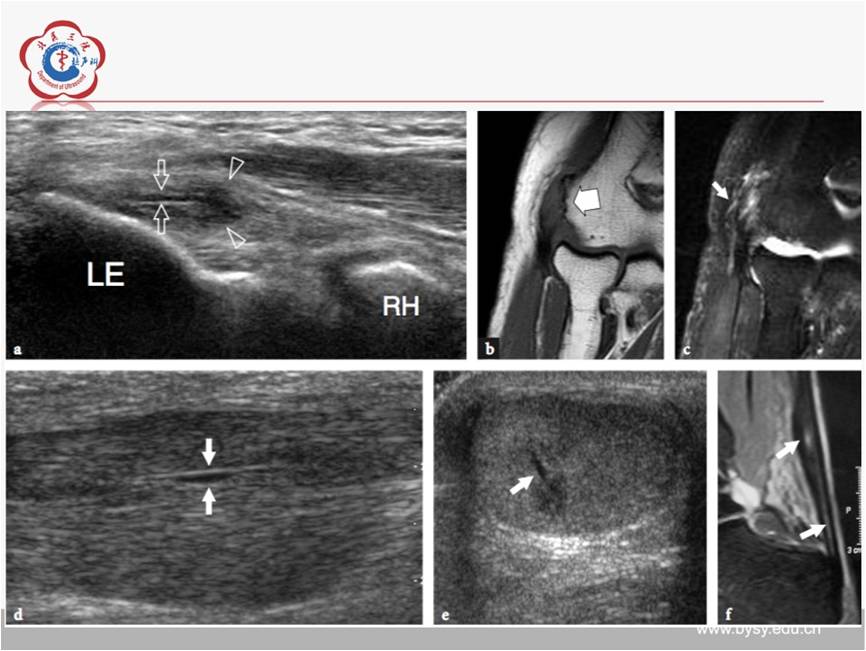

【经典超声书籍解读】肌肉骨胳超声诊断之肌腱病与部分撕裂